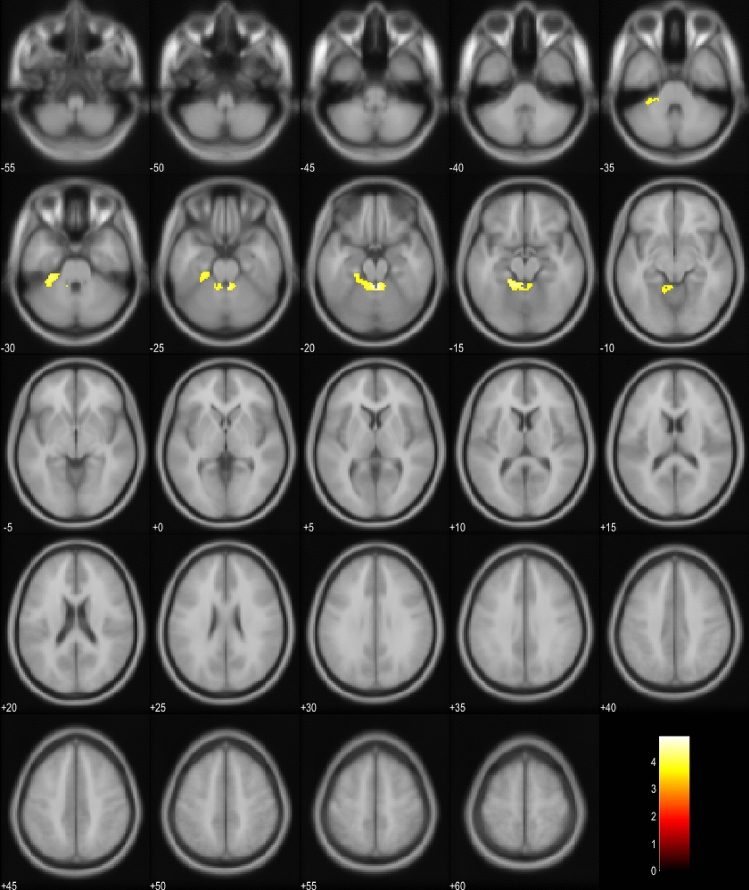

18FDG-PET scans of the EP + patients were compared to the scans of the EP- patients in the whole cohort and also in the subgroup including only bvFTD patients (Fig. 1a, b). In the whole cohort, EP + patients showed significant hypometabolism predominantly in the left hemisphere in the temporal and medial frontal lobes. In the bvFTD subgroup, similar results were obtained in the EP + patients with hypometabolism detected mostly in the left temporal lobe. Also, the SCP and the frontal lobes showed hypometabolism. Comparison between EP + bvFTD patients and patients with PSP or CBD indicated that the bvFTD patients specifically showed hypometabolism in cerebellar lingula and SCP (Fig. 1c). No differences were observed in the cortical regions.